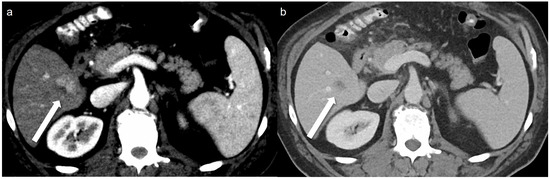

- Zhou, Y.; Xu, H.; Hou, P.; Dong, J.Q.; Wang, M.Y.; Gao, J.B. Monochromatic Spectral Computed Tomography with Low Iodine Concentration Contrast Medium in a Rabbit VX2 Liver Model: Investigation of Image Quality and Detection Rate. Acad. Radiol. 2016, 23, 486–495. [Google Scholar] [CrossRef] [PubMed]

- Nagayama, Y.; Nakaura, T.; Oda, S.; Utsunomiya, D.; Funama, Y.; Iyama, Y.; Taguchi, N.; Namimoto, T.; Yuki, H.; Kidoh, M. Dual-layer DECT for multiphasic hepatic CT with 50 percent iodine load: A matched-pair comparison with a 120 kVp protocol. Eur. Radiol. 2018, 28, 1719–1730. [Google Scholar] [CrossRef]